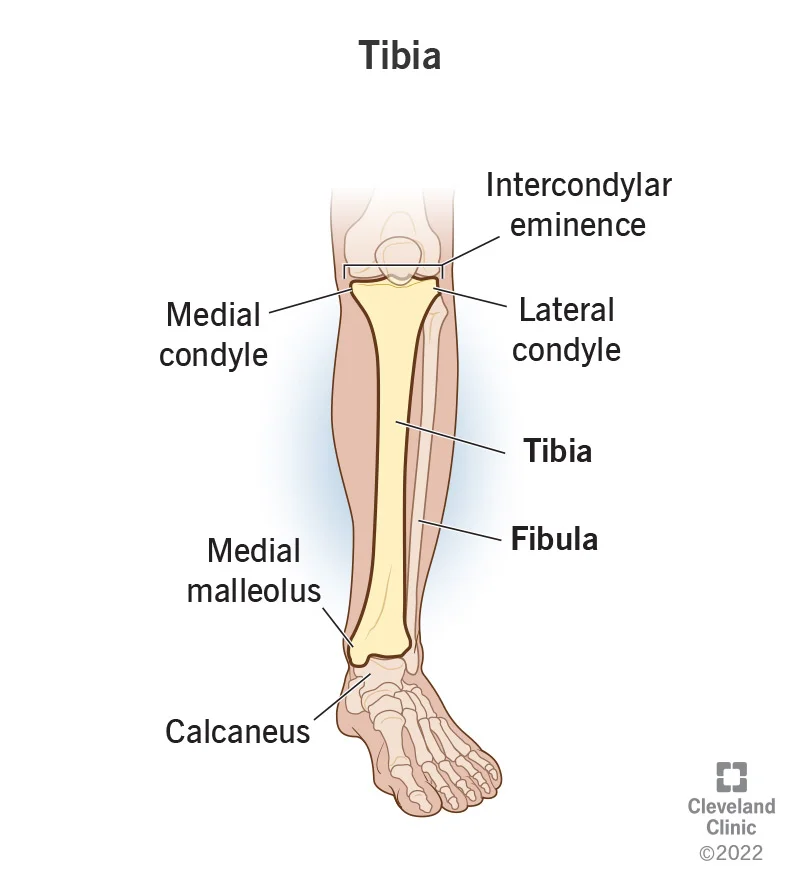

What Is the Tibia?

The tibia is your shinbone. It is the large bone below your knee.

When your knee wears unevenly (for example, on the inner side), it can make your leg look slightly bow-shaped. This puts extra pressure on one half of the joint, causing pain while walking or climbing stairs.

High Tibial Osteotomy (HTO) is a surgical procedure that gently cuts and reshapes the upper part of the tibia to shift weight back to the healthier side of the knee.